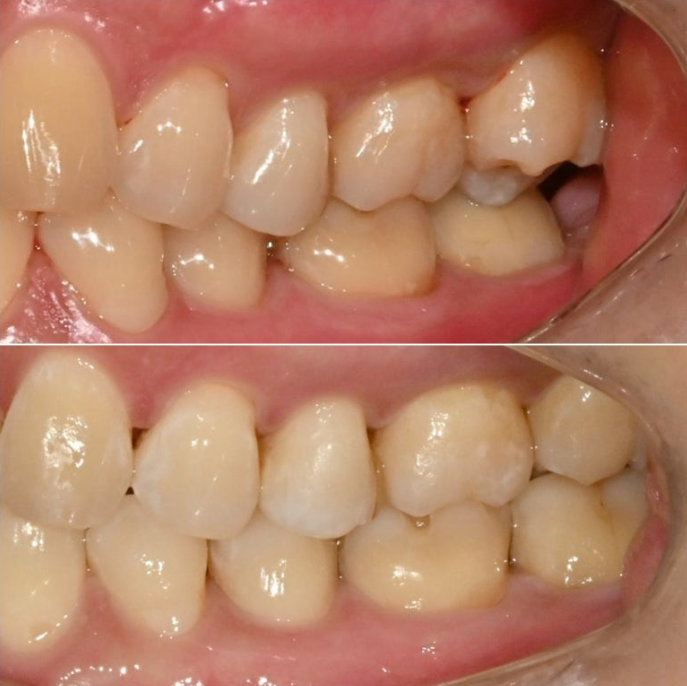

어금니가 엇갈려 교합이 안되는 상태를 가위교합 이라고 합니다.

오늘은 중심선 불일치, 가위교합, 벌어짐, 과개교합 네가지 문제를 인비절라인 라이트로 어떻게 치료하는 지 보여드리겠습니다.

앞에서 보면 윗니가 아랫니를 많이 덮어서 앞니가 깊게 물리는 과개교합, 중심선 불일치,벌어진 앞니 등이 보입니다.

파란 화살표와 같이 물리는 상태를 가위교합이라고 합니다.

맨 뒤 큰 어금니에 흔하게 보이는 부정교합입니다.

위 어금니는 배열에서 바깥으로 나가있고

아래 어금니는 안으로 쓰러져 있습니다.

경미한 총생과 중심선 불일치, 가위교합, 벌어짐, 과개교합 문제가 있는 상황입니다.

인비절라인 라이트로 충분해서 인비절라인 라이트 권유드렸습니다.

24년 12월부터 25년 4월까지 라이트 프로그램에서 허용하는 장치 14개 모두 낀 후 모습입니다.

25.04

중심선은 처음에 비해 많이 맞아졌고 여전히 약간의 불일치가 남아있습니다.

아래 작은어금니의 완벽한 회전을 위해서 고무를 걸 부가장치를 붙인채 치료를 진행했습니다.

가위교합의 빠른 해결을 위한 입천장의 교정용 나사도 썼습니다.

안으로 쓰러져 있던 큰어금니도 잘 세워졌고 가위교합도 해소가 되었습니다.

또 고무줄의 힘으로 아래 작은어금니 회정는 1차세트에서 대부분 개선이 됩니다.

중심선 일치, 미세공간 등 추가개선을 위해 추가장치 제작에 들어갑니다.

25년 5월부터 10월까지 추가장치를 모두 낀 후 치료를 마무리

25.10

정확히 일치하는 중심선이 눈에 띕니다.

과개교합은 개선되어 이제 아래 앞니가 절반 이상 보입니다.

어금니 교합은 물샐틈 없는 1급 교합관계를 보입니다.

이제 전후 볼까요

총 치료기간은 11개월에 재제작 1회 입니다.

24.11~25.10

앞니 사이 벌어진 공간은 없어졌고 다시 벌어지지 않도록 고정식 철사 유지장치로 단단히 고정되었습니다

쓰러진 큰어금니가 잘 섰습니다.

가위교합의 개선으로 서로 엇갈려 물리지 못하던 큰어금니가 이제 잘 교합이 됩니다.